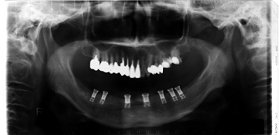

| 1-1 通法により、咬合紙と咬合調整用ワックスで調整を行った後採得したデンタルプレスケールのデータ。この時点で、患者さんは違和感を訴えることはなかった。 |

1-2 アイランドのデータをプリントアウトして実際の上部構造の上にあてがい、左右のバランス、接触点の面積、個々の接触点の咬合力を調整した後のデータ。 |

1-1と1-2の咬合力バランスを比較すると接触点の面積は3.8から3.4に減ってはいるが、むしろ咬合力は230.7Nからわずかではあるが230.8Nに増加している。患者さんは「さっきのでも十分と思ったが、より違和感のない噛み合わせになった」と話されていた。